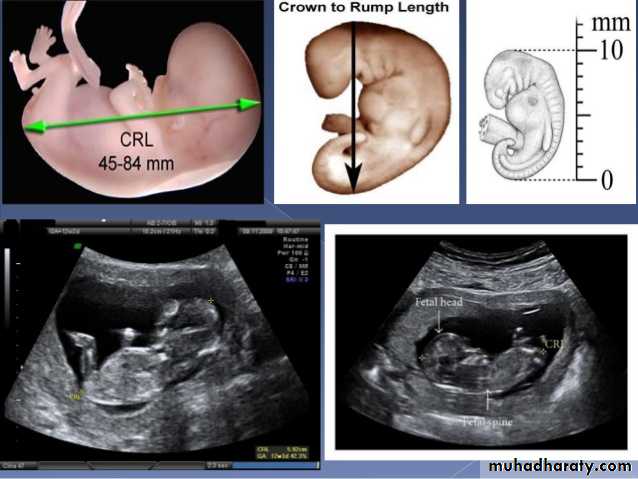

BPD together with head circumference (HC), abdominal circumference (AC), and femur length (FL) are computed to produce an estimate of fetal weight. In the second trimester this may be extrapolated to an estimate of gestational age and an estimated due date (EDD) .

The BPD should be measured on an axial plane that traverses the thalami, and cavum septum pellucidum. The transducer must be perpendicular to the central axis of the head, and thus the hemispheres and calvaria should appear symmetric.